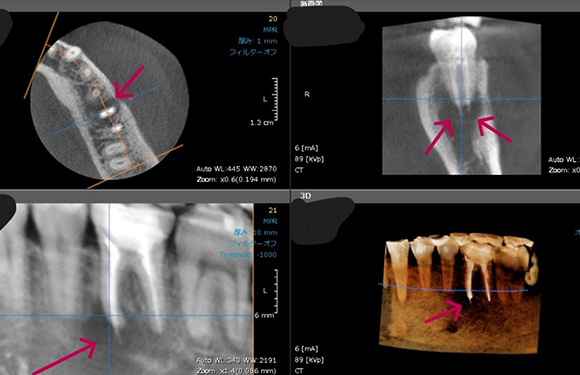

歯科用CT完備

通常、歯の状態を確認する場合、平面のレントゲン写真を使用しますが、平面のレントゲン写真では立体の歯に対して神経の管がどこにあって何本通っているかしっかりと判断することはできません。そこで、三次元的に立体画像で確認することができる歯科用CTを使用し、神経の位置や根管をしっかりと確認します。

精密な治療を皆さまへ提供するためにも、精度の高い診査・診断が重要です。

根管治療にCTはなぜ必要なのですか?

CTを使うことで「見えなかったものが見える」からです。

従来はデンタル写真やパノラマ写真で診断していましたが、これらでは根の先の病巣が映らないことも多く、

「咬むと痛い」「なんとなく違和感がある」といった症状があっても原因が分からず、不定愁訴として片づけられることもありました。

しかしCTを用いると、通常のレントゲンでは映らなかった根尖病巣がはっきり見えることが数多くあります。

つまり、「レントゲンでは異常なし」とされた歯でも、CTでは感染が確認されることが少なくありません。

さらにCTは、

• 根管の数や形の確認

• 複雑な根の走行の把握

にも非常に有効です。これにより、治療の精度と成功率が大きく高まります。

言い換えるなら、CTなしで根管治療を行うのは、羅針盤を持たずに大海原へ漕ぎ出すようなものです。

ただし、保険診療ではCT撮影に制限があり、特に前歯や小臼歯では自由に撮影できないのが現実です。当院では必要に応じて自費でのCT撮影を行い、確実に病気を見つけ、正確な治療を行う体制を整えています。